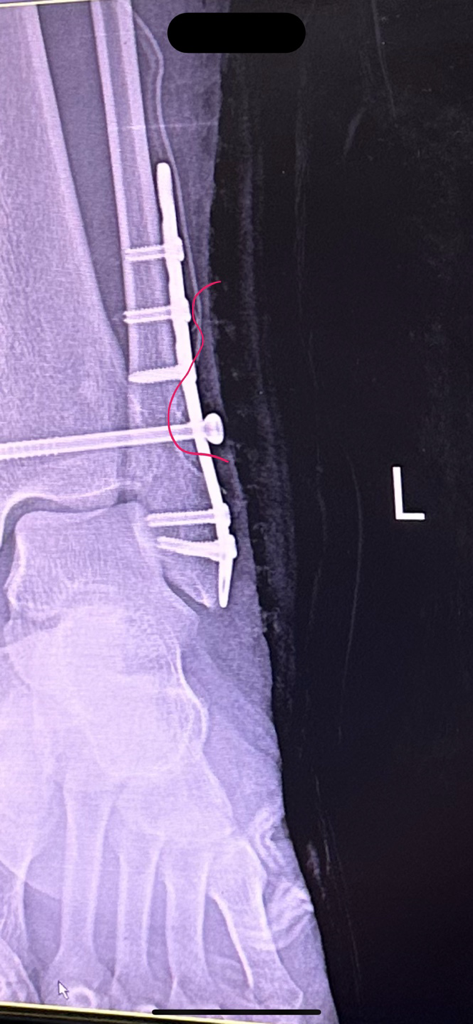

해당 엑스레이를 그당시에는 설명안하고 제가 내원했을 때 설명하시더라구요 "여기선 잘 안보여" 라고 하는데 일반인인 제가 여기있다고 말씀드렸습니다. 심지어 다른각도에서는 더 잘보이구요. 그래놓고 허겁지겁 다음 예약 잡자 말을 돌리시더라구요